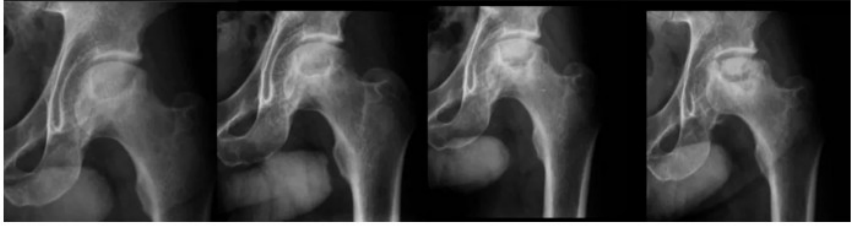

<p>Prova de Diagnostico por imagem</p><p>1. Com relação à cirurgia do sistema musculoesquelético em pequenos animais, as fraturas fisárias são classificadas de acordo com o esquema de Salter-Harris, o qual identifica a localização da linha de fratura. As fraturas que ocorrem ao longo da própria fise são classificadas como</p><p>(A) tipo I.</p><p>(B) tipo II.</p><p>(C) tipo III.</p><p>(D) tipo IV.</p><p>(E) tipo V.</p><p>2. Avalie o seguinte caso clínico: Cão da raça Yorkshire, 10 meses de idade, apresentando claudicação grau 2 no membro pélvico esquerdo e dor a palpação coxofemoral esquerda. Os exames radiográficos seriados evidenciaram as alterações ósseas reveladas nas imagens abaixo. Com base nesses dados, qual provável diagnóstico?</p><p>a. Fratura do colo femoral esquerdo.</p><p>b. Displasia coxofemoral esquerda.</p><p>c. Necrose asséptica da cabeça do Fêmur esquerdo.</p><p>d. Luxação coxofemoral esquerda.</p><p>3. Associe as imagens abaixo à classificação da fratura.</p><p>I. Fratura transversa em em terço médio de Radio e Ulna</p><p>II. Fratura transversa em em terço médio de Tíbia e Fíbula</p><p>III. Fratura transversa em terço proximal de Úmero</p><p>IV. Fratura transversa em terço médio de Úmero</p><p>V. Fratura obliqua em terço médio de Fêmur</p><p>VI. Fratura obliqua em terço médio de Tíbia</p><p>VII. Fratura de Salter Harris tipo IV em Úmero</p><p>VIII. Fratura transversa em terço médio de Fêmur</p><p>A). c, f, b, a, h, d, e, g</p><p>B). f, g, h, c, e, d, a, b</p><p>C). d, f, a, h, b, g, c, e</p><p>D). g, d, c, h, b, f, a, e</p><p>4. Qual característica física, faz diferenciar a tonalidade da imagem radiográfica dos ossos (radiopaco) em relação aos tecidos moles, com aspecto mais radioluscente (músculos e tendões)?</p><p>A densidade dos tecidos.</p><p>5. Coloque os itens a seguir em ordem de acordo com a radiopacidade (mais radoluscente para o mais radiopaco).</p><p>· Osso</p><p>· Líquido</p><p>· Ar</p><p>· Gordura</p><p>· Metal</p><p>Ar-gordura- líquido-osso-metal</p><p>6. A escala de frequência do ultrassom diagnóstico está entre:</p><p>6. A escala de frequência do ultrassom diagnóstico está entre:</p><p>a) 20 Hz a 20.000 Hz.</p><p>b) 20.000 Hz a 200.000 Hz</p><p>c) 100.000 Hz a 1.000.000 Hz.</p><p>d) 1 MHz a 15.000 MHz.</p><p>7. Sob condições técnicas alguns artefatos são essenciais para o estabelecimento da</p><p>8. interpretação da imagem. Que tipo de artefato caracteriza o diagnóstico de cálculo</p><p>9. vesical?</p><p>10. Sob condições técnicas alguns artefatos são essenciais para o estabelecimento da</p><p>11. interpretação da imagem. Que tipo de artefato caracteriza o diagnóstico de cálculo</p><p>12. vesical?</p><p>13. Sob condições técnicas alguns artefatos são essenciais para o estabelecimento da</p><p>14. interpretação da imagem. Que tipo de artefato caracteriza o diagnóstico de cálculo</p><p>15. vesical?</p><p>16. Sob condições técnicas alguns artefatos são essenciais para o estabelecimento da</p><p>17. interpretação da imagem. Que tipo de artefato caracteriza o diagnóstico de cálculo</p><p>18. vesical?</p><p>7. Sob condições técnicas alguns artefatos são essenciais para o estabelecimento da interpretação da imagem. Que tipo de artefato caracteriza o diagnóstico de cálculo vesical?</p><p>a) Reforço acústico.</p><p>b) Sombra acústica.</p><p>c) Imagem em espelho.</p><p>d) Reverberação.</p><p>8. Associe as colunas conforme o método de diagnostico e seu princípio físico básico:</p><p>a) Ressonância Magnética</p><p>9. a) Termografia (d) Radiação X</p><p>10. b) Ressonancia magnética (f) Fonte de luz + câmera</p><p>11. c) Tomografia computadorizada (e) Radiofármaco (radiação gama/beta)</p><p>12. d) Radiografia convencional</p><p>13. a) Termografia (d) Radiação X</p><p>14. b) Ressonancia magnética (f) Fonte de luz + câmera</p><p>15. c) Tomografia computadorizada (e) Radiofármaco (radiação gama/beta)</p><p>16. d) Radiografia convencional</p><p>b)Tomografia Computadorizada</p><p>c) Radiografia convencional</p><p>d)Ultrassonografia</p><p>(c) Radiação X</p><p>(a ) Campo magnético+ radiofrequência</p><p>(d) Onda Sonora</p><p>( b) Radiação X+ feixes</p><p>9. Em uma avalição radiográfica de tórax para se observar a integridade pulmonar quais os posicionamentos ideias para se ter uma boa visibilidade desse órgão e em qual momento é melhor para fazer o disparo? Justifique sua resposta.</p><p>Latero-lateral esquerdo e direito e ventro-dorsal. O melhor momento para fazer o disparo no RX de tórax é na inspiração, pois nesse momento o pulmão está mais expandido e a área de avaliação é maior.</p><p>10. Cite os posicionamentos radiográficos utilizados para avaliação em um cão com suspeita de displasia coxofemoral.</p><p>11. 8 – Em relação ao sistema locomotor, marque a alternativa incorreta.</p><p>( ) Uma das metodologias usadas para avaliar casos de displasia coxofemoral é a técnica de</p><p>PennHip para medir frouxidão articular, sendo necessário o uso de distrator em uma das</p><p>projeções.</p><p>( ) O método de Norberg-Olson é utilizado para avaliar o ângulo entre a cabeça femoral e o</p><p>acetábulo, onde usa-se a projeção ventrodorsal com os membros pélvicos estendidos.</p><p>( ) Na suspeita de displasia de cotovelo devemos fazer radiografia dos membros torácicos em</p><p>3 projeções: crânio-caudal, médio-lateral estendida e flexionada.</p><p>(X) Em casos de luxação de patela, devemos usar as projeções médio-lateral e crânio-caudaL</p><p>para avaliar a região como um todo. (Necessário também fazer a skyline)</p><p>( ) Nenhuma das alternativas</p><p>8 – Em relação ao sistema locomotor, marque a alternativa incorreta.</p><p>( ) Uma das metodologias usadas para avaliar casos de displasia coxofemoral é a técnica de</p><p>PennHip para medir frouxidão articular, sendo necessário o uso de distrator em uma das</p><p>projeções.</p><p>( ) O método de Norberg-Olson é utilizado para avaliar o ângulo entre a cabeça femoral e o</p><p>acetábulo, onde usa-se a projeção ventrodorsal com os membros pélvicos estendidos.</p><p>( ) Na suspeita de displasia de cotovelo devemos fazer radiografia dos membros torácicos em</p><p>3 projeções: crânio-caudal, médio-lateral estendida e flexionada.</p><p>(X) Em casos de luxação de patela, devemos usar as projeções médio-lateral e crânio-caudaL</p><p>para avaliar a região como um todo. (Necessário também fazer a skyline)</p><p>( ) Nenhuma das alternativas</p><p>11. Em relação ao sistema locomotor, marque a alternativa incorreta.</p><p>( ) Uma das metodologias usadas para avaliar casos de displasia coxofemoral é a técnica de PennHip para medir frouxidão articular, sendo necessário o uso de distrator em uma das projeções.</p><p>( ) O método de Norberg-Olson é utilizado para avaliar o ângulo entre a cabeça femoral e o acetábulo, onde usa-se a projeção ventrodorsal com os membros pélvicos estendidos.</p><p>( ) Na suspeita de displasia de cotovelo devemos fazer radiografia dos membros torácicos em 3 projeções: crânio-caudal, médio-lateral estendida e flexionada.</p><p>( X) Em casos de luxação de patela, devemos usar as projeções médio-lateral e crânio-caudaL para avaliar a região como um todo. (Necessário também fazer a skyline)</p><p>( ) Nenhuma das alternativas</p><p>Termografia (d) Radiação X</p><p>b) Ressonancia magnética (f) Fonte de luz + câmera</p><p>c) Tomografia computadorizada (e) Radiofármaco (radiação gama/beta)</p><p>d) Radiografia convencional</p><p>image1.png</p><p>image2.png</p>